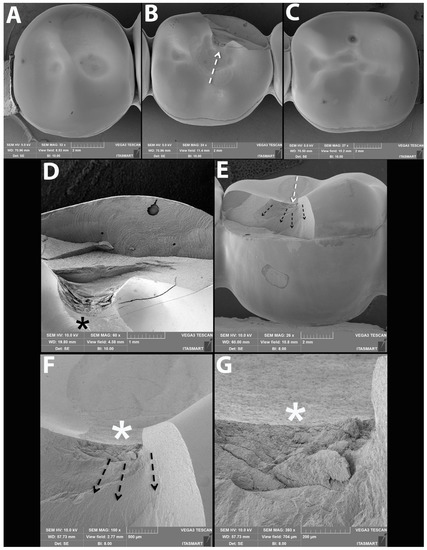

3.3. Failure and Fractographic Analysis after Single Load to Failure Testing

| Bulk fracture within connector | 10/10 (100%) | 10/10 (100%) | 10/10 (100%) | 10/10 (100%) | 8/10 (80%) | 10/10 (100%) | 3/10 (30%) | 1/10 (10%) |

| Bulk fracture without connector | - | - | - | - | 2/10 (20%) | - | - | - |

| Chipping | - | - | - | - | - | - | 7/10 (70%) | 9/10 (90%) |